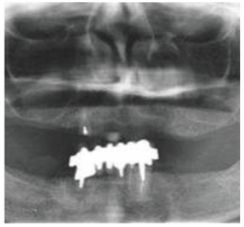

種牙前X光片

這一位老先生則選擇了All-on-4種植技術(shù),即拔即種,上下頜分別種植4個(gè)植體就完成了全口牙齒修復(fù),費(fèi)用降低了不少,而且創(chuàng)傷小,恢復(fù)快。